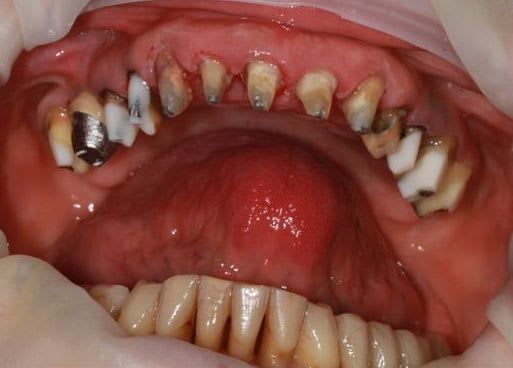

dépose des ceramo métal antérieur, ouf le précédent n'a pas mis d'IC, j'ai plus de marge de manœuvre.

Prochaine étape réalisation d'un provisoire résine "complet" pour le max.sup., mais il me faut paralléliser tous les moignons.

j'en suis à la 4eme séance détartrage surface...et ça commence à être propre et sain.